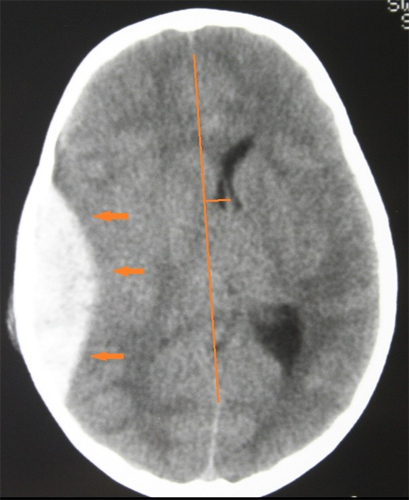

What is a cerebral hemorrhage?

Bleeding inside the brain; a medical emergency.

What causes cerebral hemorrhage in trauma?

Vessel damage from rapid acceleration/deceleration (e.g., MVA, shaken baby syndrome).

What complication can large bleeds cause on CT?

Midline shift of the Falx Cerebri.

Name two serious outcomes of untreated cerebral hemorrhage.

Paralysis and death.

What is the difference between arterial and venous cerebral hemorrhages on CT?

Arterial bleeds are faster, larger, and cause more mass effect; venous bleeds may be slower and smaller.